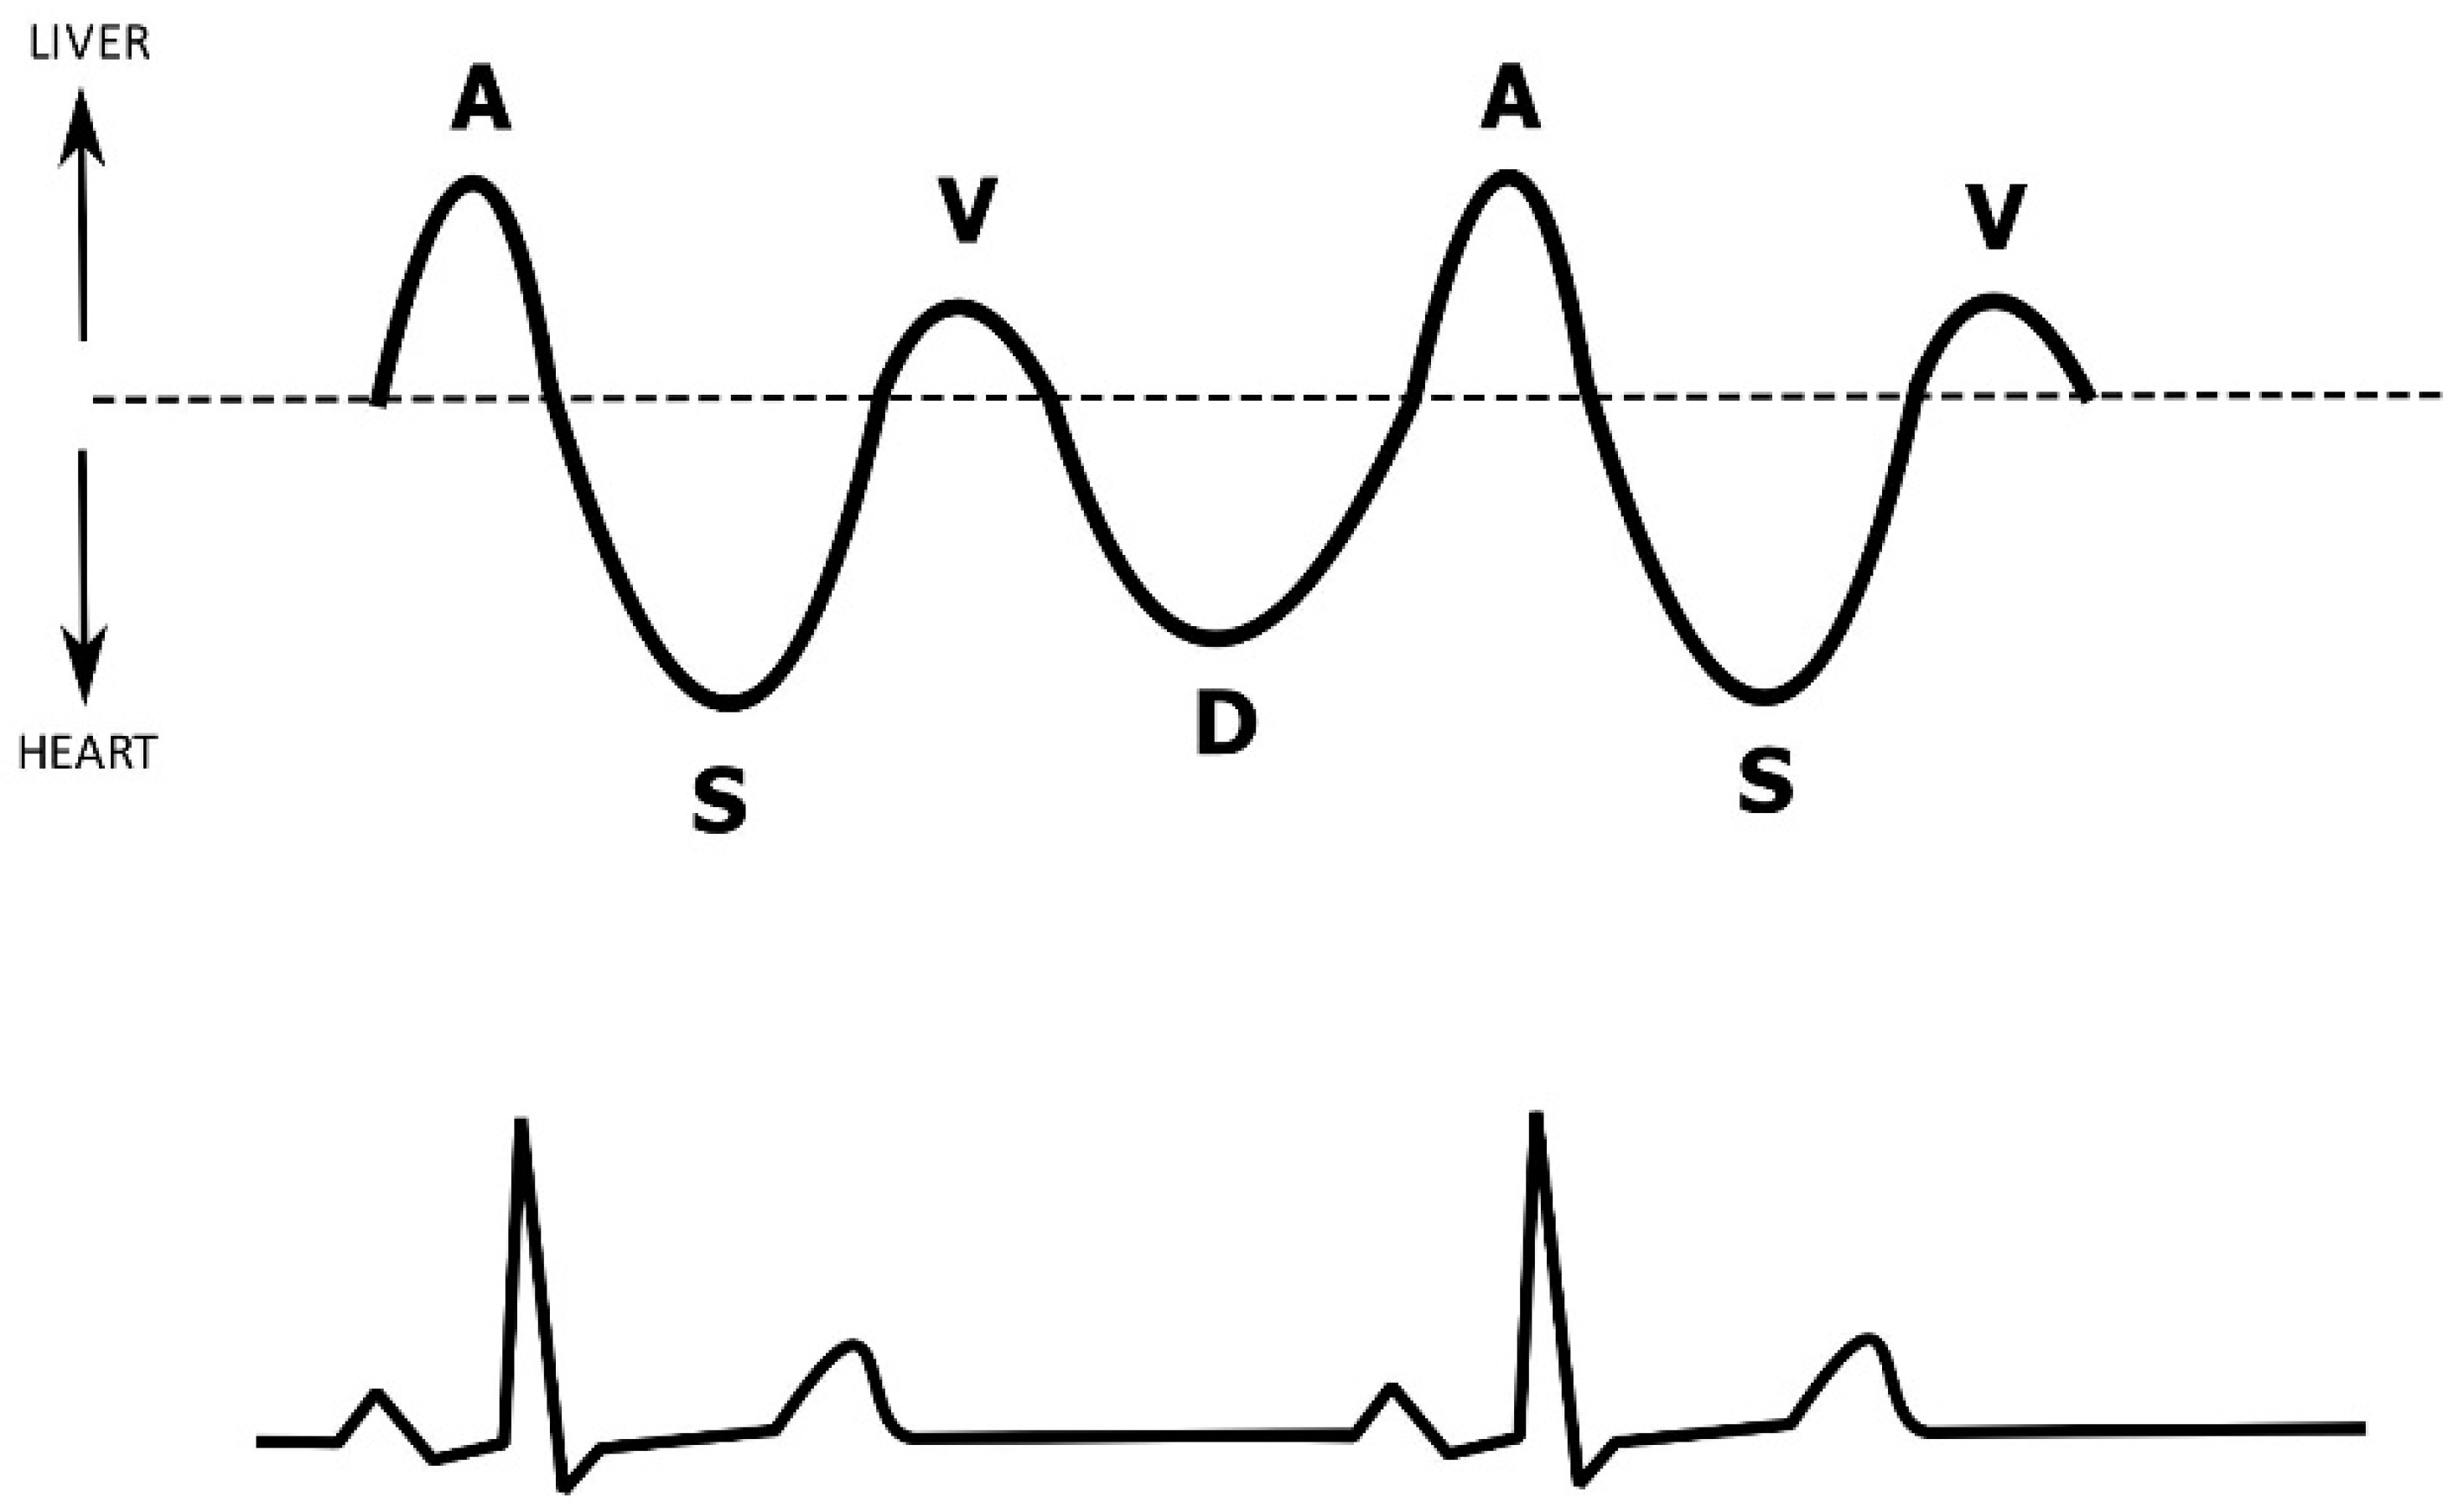

5. Hepatic Venous Flow